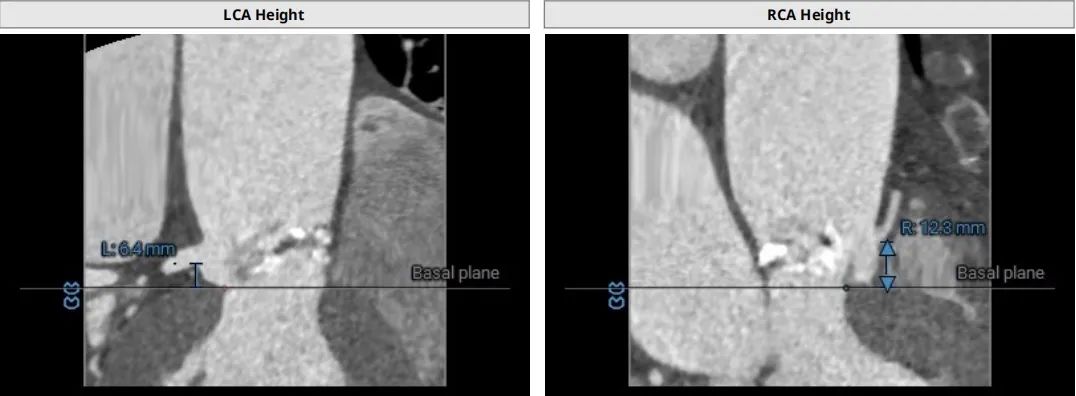

CT术前评估

主动脉根部情况

瓣上2mm--8mm 瓣上结构

左冠高度6.4mm 右冠脉高度12.3mm

♦ 左右冠脉开口高度分别为6.4mm和12.3mm,左右瓣叶长,冠脉风险高,需球扩时评估是否需要冠脉保护;